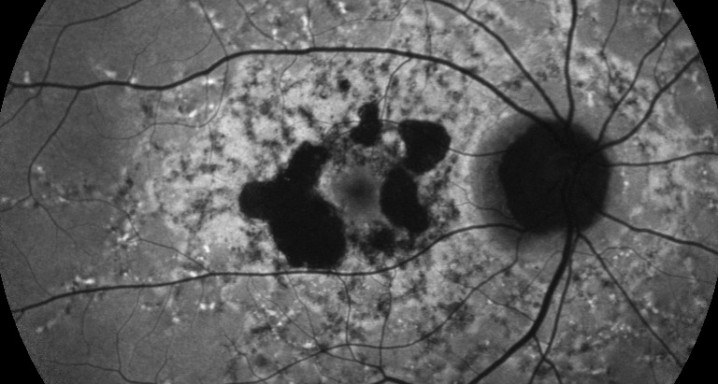

OPH2005 es un estudio en fase 2b randomizado, doble enmascarado para establecer la eficacia y la seguridad de Zimura™ en comparación con placebo en sujetos diagnosticados de enfermedad de Stargardt de herencia autosómica recesiva.

El objetivo del estudio evaluará la diferencia entre el cambio del área del defecto de la elipsoide medida con OCT.